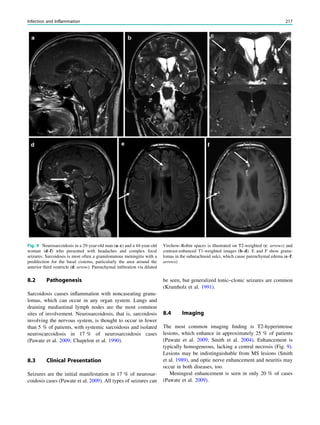

How to Perform MRI 33

thick coronal slices have a slightly lower contrast-to-noise

ratio than the corresponding 2D slices.

High-resolution T2-weighted fast spin echo images have

both high spatial resolution and a high contrast-to-noise

ratio. They are particularly suited to assess white matter

lesions. However, since CSF is also bright, hyperintense

cortical lesions can be easily missed.